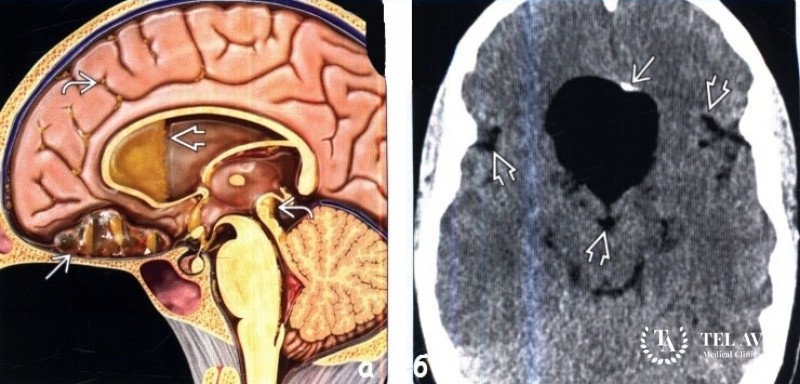

Как диагностировать дермоидную кисту мозга

Первичная диагностика дермоидной кисты основывается на сборе анамнеза. Специалист опрашивает, осматривает пациента, используя пальпацию. Необходимо провести забор крови на биохимический анализ. Среди информативных методов выявления патологии выделяют:

- Магнитно-резонансную томографию;

- Компьютерную томографию.